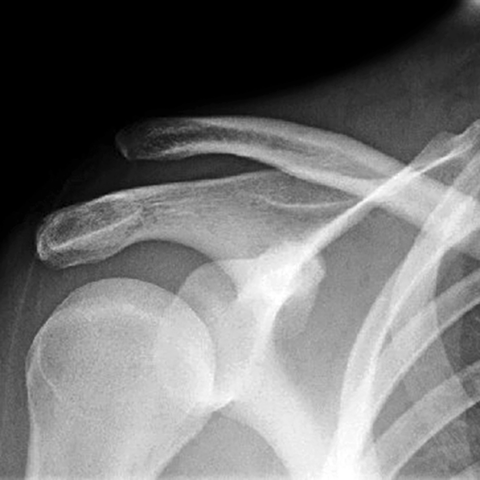

Acromioclavicular dislocation